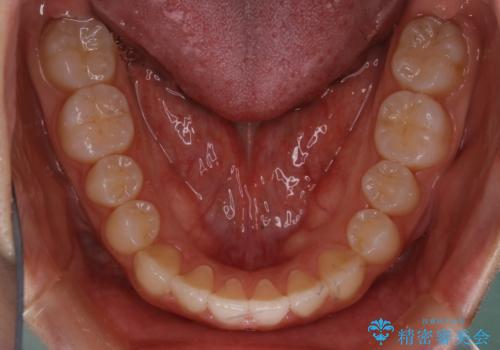

- 受け口の改善と前歯のガタつきの治療を主訴にご来院されました。

こちらの患者様の場合、上の前歯のガタつきが原因で口を閉じる際に上下の前歯の先端同士が先に当たってしまい、そこからさらに深く噛み込もうとすると下顎が前にずれていってしまうという、機能性の反対咬合であることが検査の結果わかりました。

そのため、まずは上顎の前歯のガタつきを改善していき、前歯が先に当たってしまうという症状を改善し噛み込む位置を後方の本来の位置に誘導する方法をとりました。